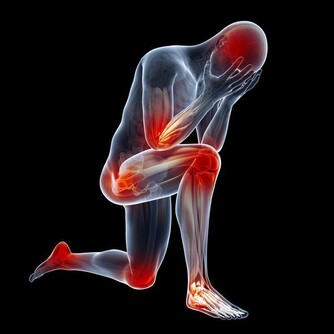

3。吃海鮮時不要喝啤酒

啤酒和海鮮發生反應,會使身體內的尿酸含量迅速升高,對於本身就高尿酸的人來說,容易導致痛風發作。現在,很多三四十歲的中青年人,都有脂肪肝、高血脂、高尿酸等代謝疾病,與不良飲食習慣關係密切。